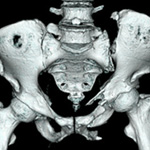

股関節

Hip joint

上聖マリアンナ医科大学整形外科学講座の股関節外科班は平成7年に2代目主任教授 青木治人 先生によって設立されて、3代目主任教授 別府諸兄 先生に引き継がれました。そして4代目主任教授の仁木久照 先生によって平成29年度から新しいコンセプトをもった股関節班が誕生しました。これまでは治療は主に人工股関節全置換術を中心に行われており、安定した手術成績で患者さんに貢献して参りましたが今後はさらに股関節温存手術(骨切り術・股関節鏡視下手術)にも注力して小児から高齢者まで年齢の幅を超え、骨盤寛骨臼骨折・スポーツ外傷から慢性疾患まで幅広い疾患に対応できる最先端の「全方向性」股関節班に生まれ変わります。・・・